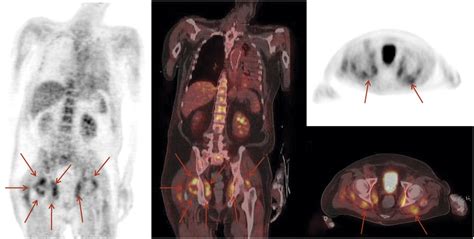

Now, let’s talk about what the doctors actually see when they look at these scans, specifically regarding inflammation. When a radiologist or nuclear medicine physician interprets a PET scan, they’re looking for areas where the FDG tracer has accumulated more than expected. These areas of increased tracer uptake are often referred to as ‘hot spots’ and are the primary indicators of inflammation on a PET scan. However, it’s not always as simple as a bright spot automatically meaning active inflammation. Context is everything , guys. The interpretation needs to be done by experienced professionals who understand the nuances. For instance, certain normal physiological processes can also lead to increased FDG uptake. Think about the brain – it’s naturally a high-metabolism organ, so it will always show up brightly on a PET scan. Similarly, the bladder and kidneys will often show high uptake because they are involved in excreting the tracer. Muscles can also show increased uptake if they’ve been recently exercised. Therefore, the interpreting physician compares the pattern and intensity of the uptake to known normal patterns and considers the patient’s clinical history and symptoms. They’ll be looking for uptake in locations that are unexpected, in patterns that are characteristic of specific inflammatory diseases, or uptake that is significantly higher than in surrounding tissues. For example, in vasculitis, they might see increased uptake along the walls of blood vessels. In cases of infection, the hot spots might appear in a specific organ or soft tissue. They also consider the intensity of the uptake – a very bright, focal spot is more likely to represent significant pathology than a mild, diffuse increase. Sometimes, PET scans are combined with CT scans (PET/CT) to provide both functional and anatomical information, helping to pinpoint exactly where the metabolic activity is occurring within the body’s structures. This combination is incredibly powerful for accurate localization and characterization of inflammatory processes. It’s a complex puzzle, but when pieced together correctly, it provides invaluable information for diagnosing and managing conditions involving inflammation.